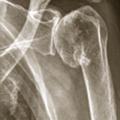

Omarthrose centrée

ARTHROSE

EPAULE